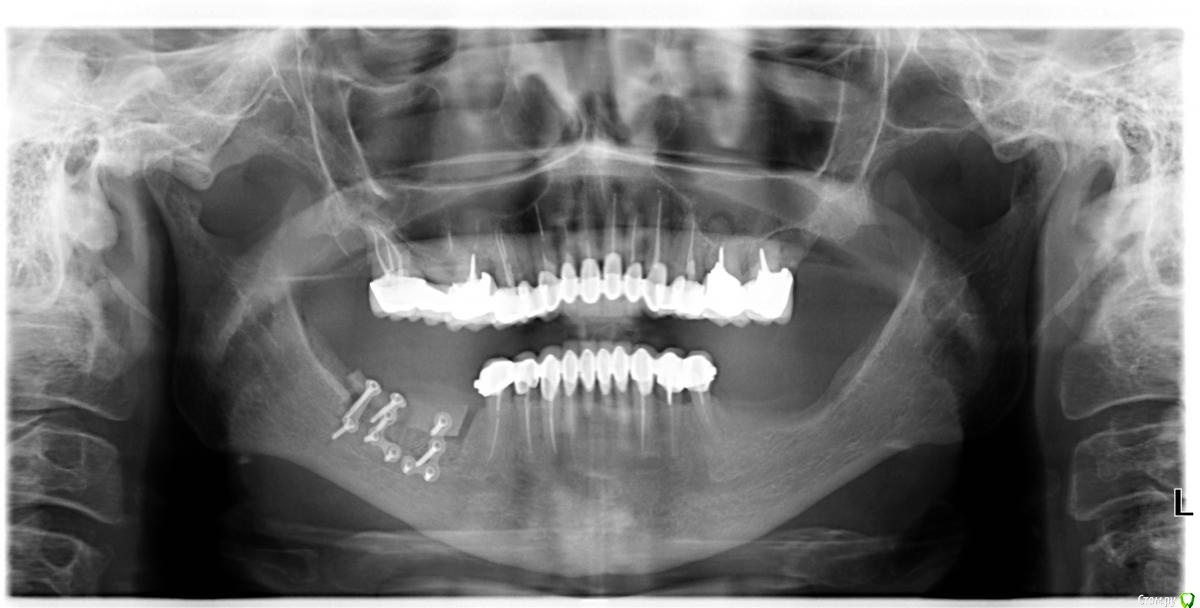

Глеб Митрофанов Опубликовано 22 октября, 2015 Автор Поделиться Опубликовано 22 октября, 2015 Срезы кт Ссылка на комментарий

basha.ru Опубликовано 23 октября, 2015 Поделиться Опубликовано 23 октября, 2015 Спасибо за кейс.Скажите пожалуйста какая высота кости до нижнечелюстного канала?Спасибо. Ссылка на комментарий

Глеб Митрофанов Опубликовано 23 октября, 2015 Автор Поделиться Опубликовано 23 октября, 2015 (изменено) Спасибо за кейс.Скажите пожалуйста какая высота кости до нижнечелюстного канала?Спасибо.До канала , в самой низшей точке - 4,5-5 мм Изменено 23 октября, 2015 пользователем Глеб Митрофанов Ссылка на комментарий